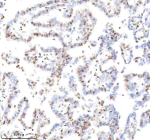

Immunohistochemical staining of Histone H3 using anti-Histone H3 (acetyl K9) antibody. Histone H3 (acetyl K9) was detected in a paraffin-embedded section of human lung cancer tissue. Heat mediated antigen retrieval was performed in EDTA buffer (pH 8.0, epitope retrieval solution). The tissue section was blocked with 10% goat serum. The tissue section was then incubated with 1:50 rabbit anti-Histone H3 (acetyl K9) antibody overnight at 4oC. Peroxidase Conjugated Goat Anti-rabbit IgG was used as secondary antibody and incubated for 30 minutes at 37oC. The tissue section was developed using an HRP secondary and DAB substrate.